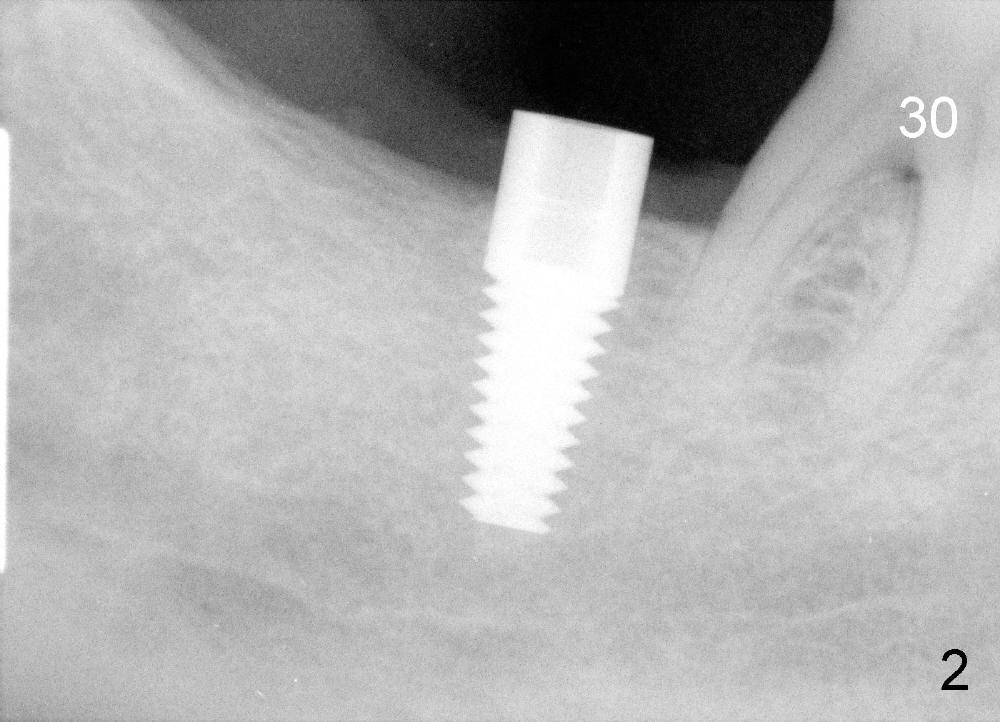

Mr. Liu has lost the tooth #29 for a while. The tooth #30 has shifted mesially (Fig.1 arrow). An implant is placed distal to it (Fig.2). Orthodontics has started to upright the tooth #30, but he does not want to finish the treatment.